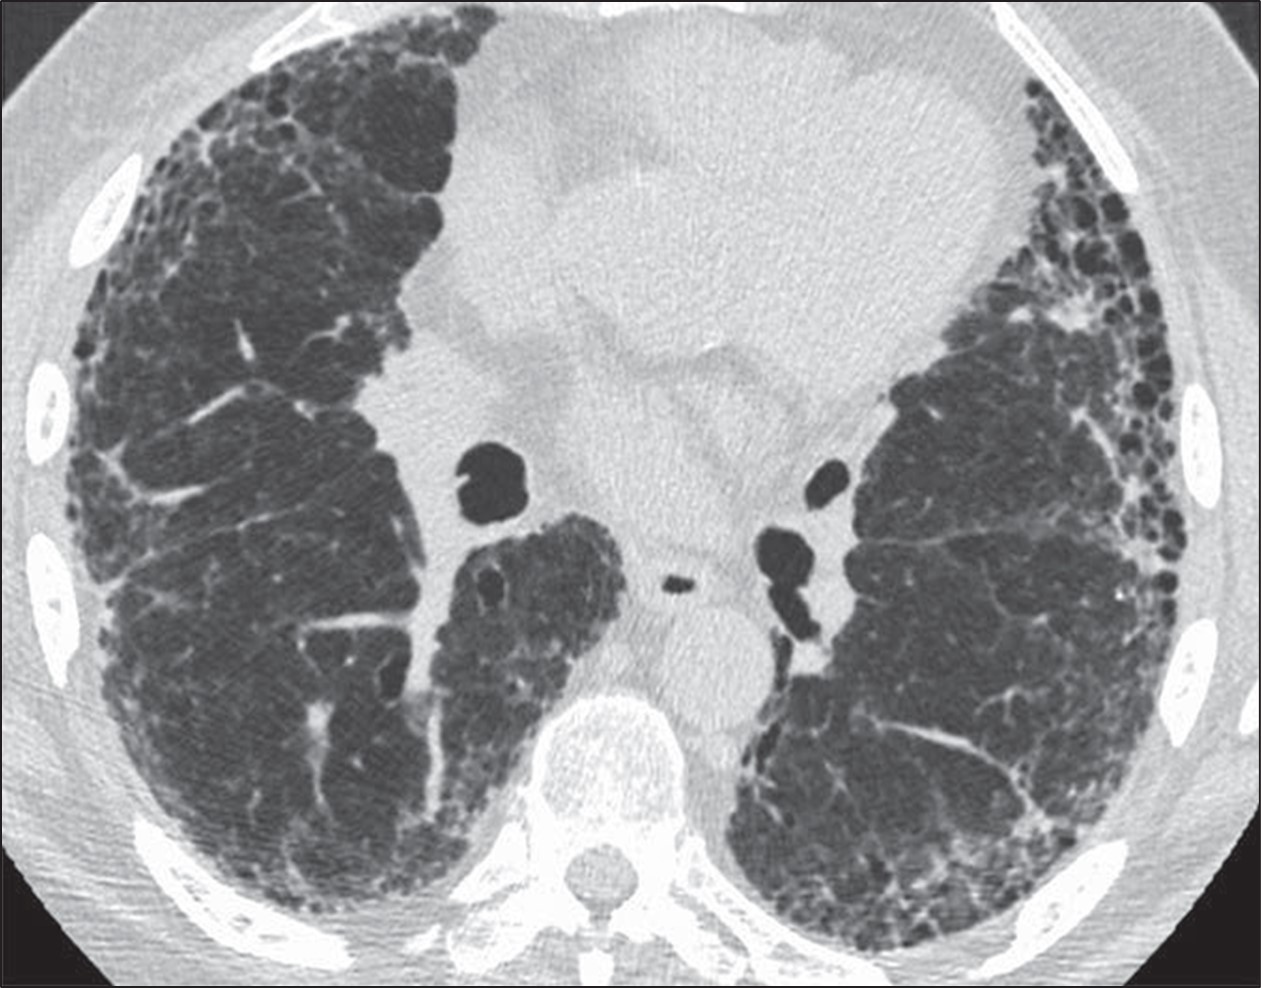

A 52-year-old man comes to the physician because of a 6-month history of shortness of breath and nonproductive cough. He has smoked 1 pack of cigarettes daily for 15 years. Cardiopulmonary examination shows fine inspiratory crackles bilaterally. There is clubbing present in the fingers bilaterally. Pulmonary function tests (PFTs) show an FVC of 78% of expected and an FEV1/FVC ratio of 92%. A CT scan of the chest is shown. Which of the following is the most likely underlying diagnosis?